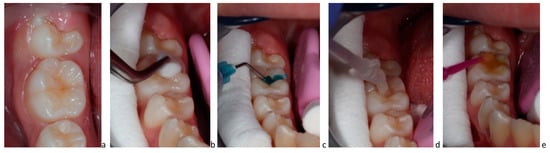

7. Perspectives for Treatments with P11-4

- Alkilzy, M.; Santamaria, R.; Schmoeckel, J.; Splieth, C. Treatment of Carious Lesions Using Self-Assembling Peptides. Adv. Dent. Res. 2018, 29, 42–47. [Google Scholar] [CrossRef]